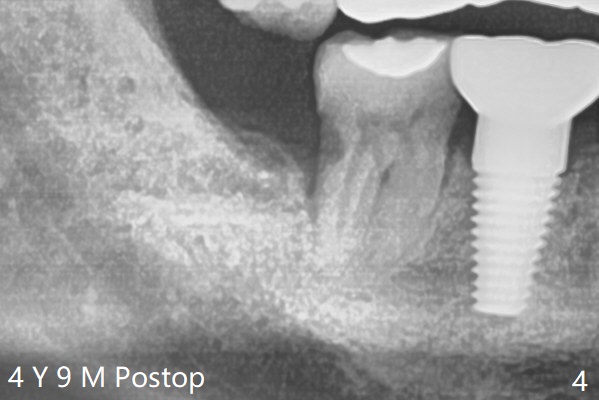

A 40-year-old man had the tooth #32 extracted without bone graft immediate post #30 implant placement (Fig.1,2). The distal bony defect of the tooth #31 appears to have been repaired 4 years postop (Fig.3,4).